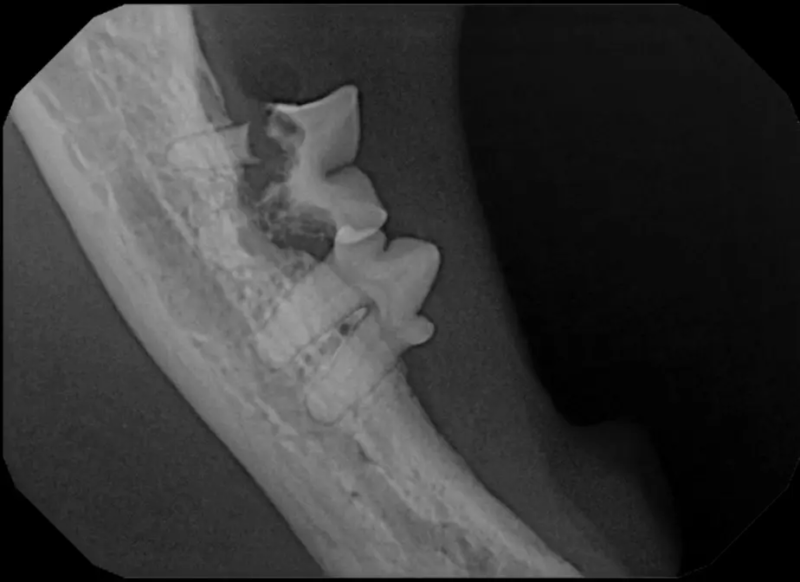

Tooth resorption is a disease process where the body begins to break down the adult tooth. It is widely known to occur in cats but can also occur in dogs. In cats these lesions are thought to be inflammatory, while in dogs they can be more of a replacement resorption process. These lesions can be very painful and should be treated, generally with extraction depending on the type of resorption that is occurring. The disease can be progressive and affect many teeth over several years. It is important to have regular checkups and yearly dental cleanings to monitor for these lesions.